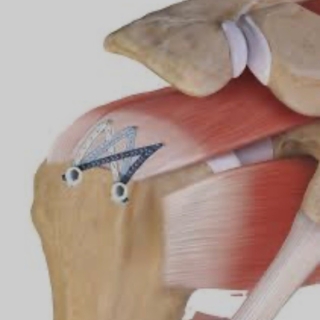

Στη συνέχεια, ο τένοντας σταθεροποιείται στο οστό με τη χρήση αγκυρών (anchors), ενώ παράλληλα αντιμετωπίζονται τυχόν συνοδές βλάβες.

Συρραφή-καθήλωση του υπερακανθίου με βιοαπορροφήσιμη άγκυρα